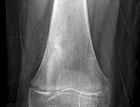

9 year old female c/o R distal femoral pain for 4 weeks. The pain occurs while sleeping and resting.

Zoom image: Radiological image Radiological image.